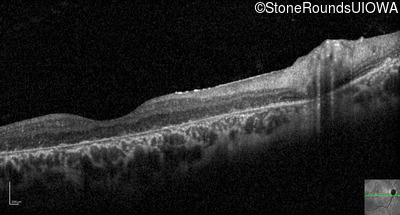

Optical Coherence Tomography - Left - 10/125 -2 sc

Exemplar / OCT Stack